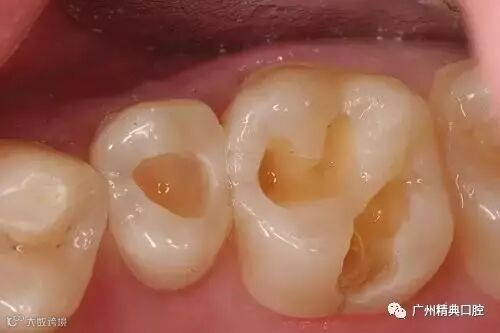

小龋洞可能不会引起疼痛

未必会引起患者注意

较大的龋洞就会因残留食物的细菌

和冷、热、酸、甜食物的刺激

引起牙疼了

口腔中的细菌可以在牙齿表面堆积形成牙菌斑生物膜,其中的致病菌分解唾液中的糖产酸,酸会破坏牙齿,形成龋洞。

此时龋洞需要进行充填,否则会继续被侵蚀,导致牙神经损伤甚至牙神经死亡,感染或发生脓肿。因此,牙神经损伤需要进行根管治疗。